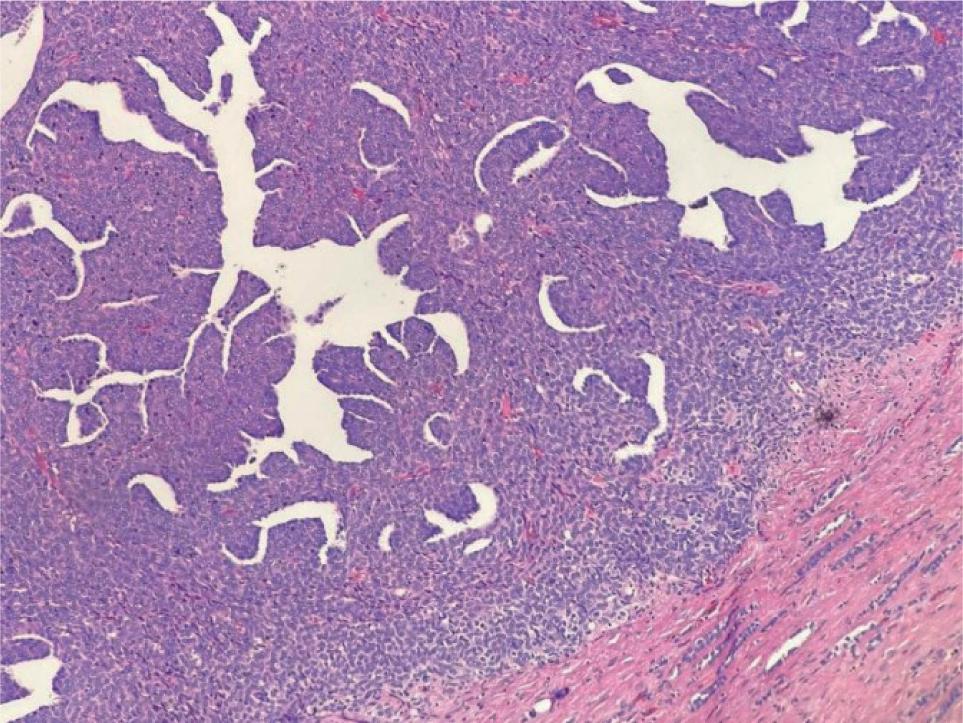

Figure 6: Microscopic picture of Wilm’s tumour showing blastemal and mesenchymal components.

Figure 7: Microscopic picture showing clear cells and increase vascularity in Clear Cell RCC.

Neoplastic lesions constituted 280 patients. Clear renal cell carcinoma (RCC) was the commonest (150 cases) followed by papillary RCC (51 cases), chromophobe (13 cases), collecting duct (7 cases), sarcomatoid (10 cases), medullary (3 cases), leiomyosarcoma (4 cases) and deposits of squamous cell carcinoma (SCC; 2 cases). Benign tumours included in the study were oncocytoma (15 cases) and angiomyolipoma (10 cases). There were 15 cases of Wilms tumour. Considering age, distribution of RCC was wide from 11–80 years with a definite peak in 5th decade (40–49 years).

The present study had 150 patients of clear RCC, which was the commonest malignant lesion among adults, followed by papillary RCC (51 patients). Chromophobe RCC was observed in 13 patients, collecting duct RCC in 7, sarcomatoid in 10, medullary RCC in 3, leiomyosarcoma in 4 and deposits of SCC in (2 patients. This was similar to results of the study conducted by Aiman A et al(11), where the clear cell type of renal carcinoma was the predominant tumour observed microscopically in 20 (80%) patients.